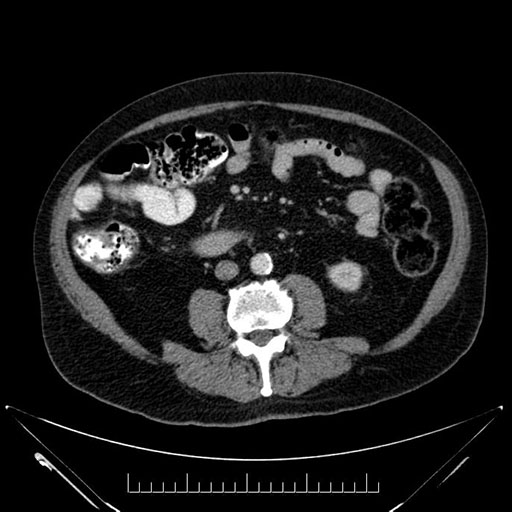

Axial - 3 months prior